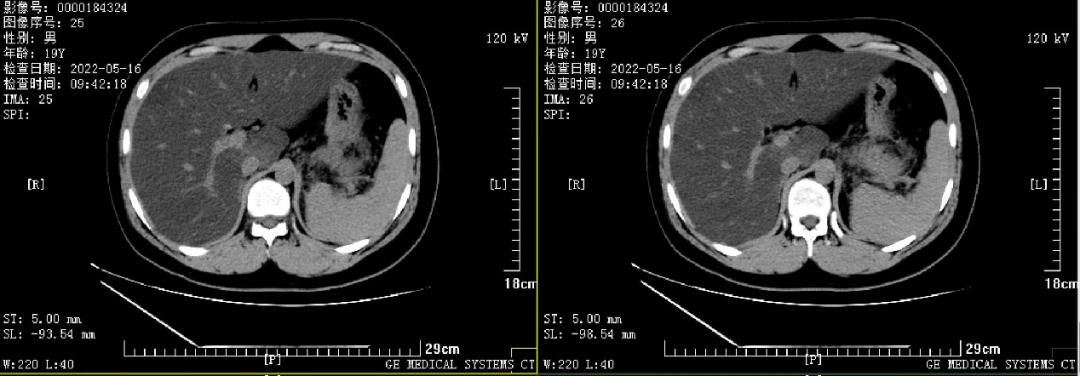

患者的腹部CT提示重度脂肪肝